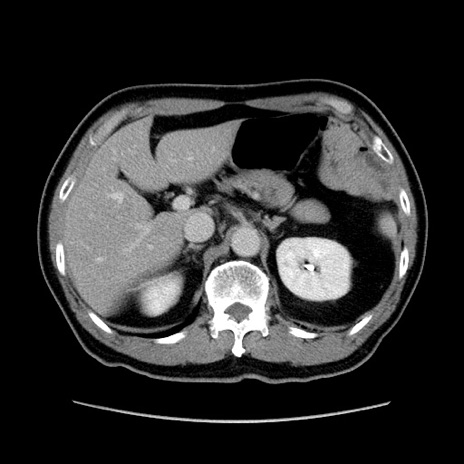

冠状断像

【症例】60歳代 男性

【主訴】右鼠径部膨隆

【現病歴】1年程前より右鼠径部膨隆あり。自己にて還納可能だったため放置していた。3時間前より右鼠径部の脱出を認め、還納困難となり受診。

【既往歴】高血圧

【身体所見】右鼠径部に小児頭大の膨隆あり。弾性硬であり、用手還納は困難。左鼠径部にも膨隆を認める。脱出はなし。

【データ】WBC 15500、CRP 測定なし